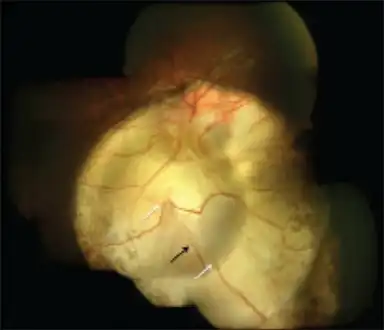

Coloboma in a 16-year-old female

Typically a coloboma appears oval- or comet-shaped with round end towards the centre. There may be a few vessels (retinal or choroidal) at the edges. The surface may have irregular depression.